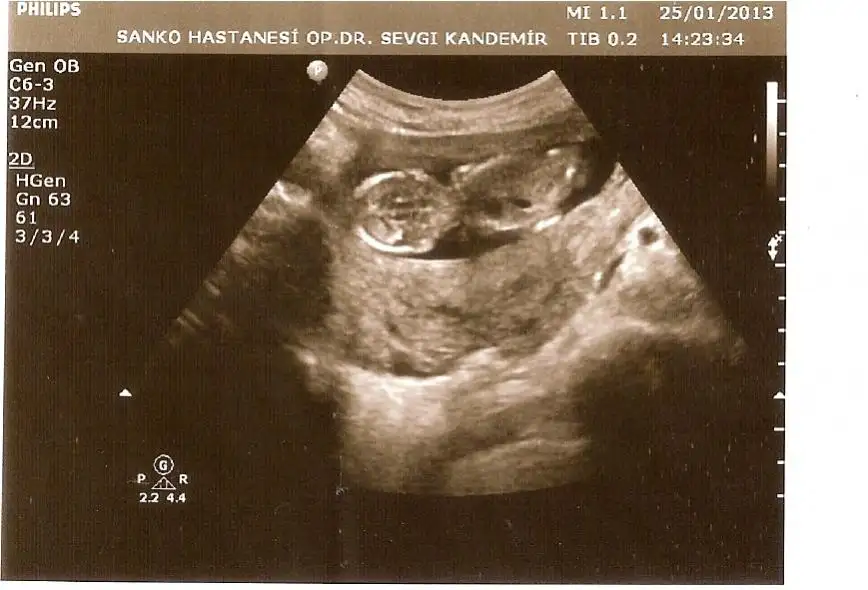

dr soylemeden siz gorun genital nub teorisi ( bebegin cinsiyeti)

Ikinci resim resmen erkek cnm kac haftaliksiniz tahmindemi yapmadi erkek gibi siz daha nt goruyosunuzdur resimden cikinti yukarda farkindaysaniz

Şimdi biz 14 hafta 2 günlüyüz.Eşimle oturub baktık iyice.Belki ben yalnış görürüm diye söyledim o baksın)))beyaz bişey var yukarda.O mu çıkıntı acaba?

Valla cnm senin bebek kiz cikarsa bayaa sasiririm ikinci resme dikkatle bak resmen yukari bakiyor cikinti